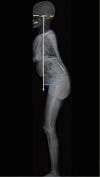

In adult spinal deformity (ASD) surgery, mechanical failure (MF) has been a significant concern for spine surgeons as well as patients. Despite earnest endeavors to prevent MF, the absence of a definitive consensus persists, owing to the intricate interplay of multifarious factors associated with this complication. Previous approaches centered around global spinal alignment have yielded limited success in entirely forestalling MF. These methodologies, albeit valuable, exhibited limitations by neglecting to encompass global balance and compensatory mechanisms within their purview. In response to this concern, an in-depth comprehension of global balance and compensatory mechanisms emerges as imperative. In this discourse, the center of gravity and the gravity line are gaining attention in recent investigations pertaining to global balance. This narrative review aims to provide an overview of the global balance and a comprehensive understanding of related concepts and knowledge. Moreover, it delves into the clinical ramifications of the contemporary optimal correction paradigm to furnish an encompassing understanding of global balance and the current optimal correction strategies within the context of ASD surgery. By doing so, it endeavors to furnish spine surgeons with a guiding compass, enriching their decision-making process as they navigate the intricate terrain of ASD surgical interventions.